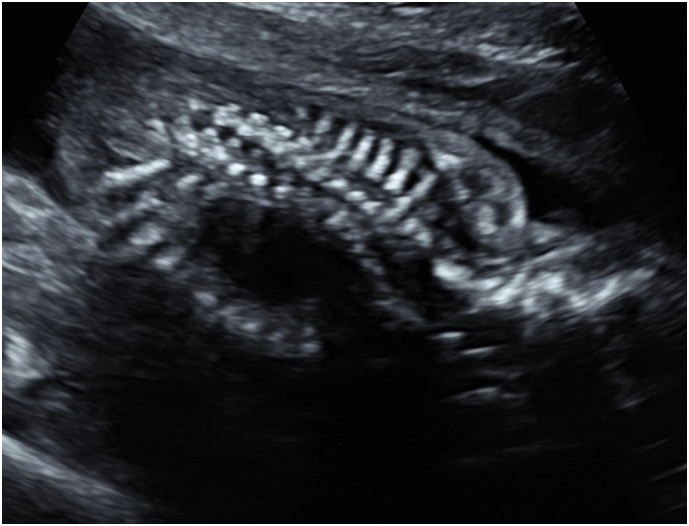

A 29-year-old woman, gravida 3 para 2, was referred to a fetal diagnosis center at 21 weeks of gestation for evaluation of a fetal cystic chest mass. The patient's medical history and family history were noncontributory. Ultrasound revealed a cystic mass in the right thorax measuring 1.9 × 2.1 × 2.6 cm. (Fig. 1), presumed to be a right congenital pulmonary airway malformation (CPAM). The spine images were limited but one area of the cervical thoracic spine on ultrasound was suspicious for dysraphism (Fig. 2). Fetal echocardiogram was normal and no other anomalies were identified.

Fig. 2.

Sonographic image of fetal spine at 21 weeks of gestation demonstrating spine dysraphism.